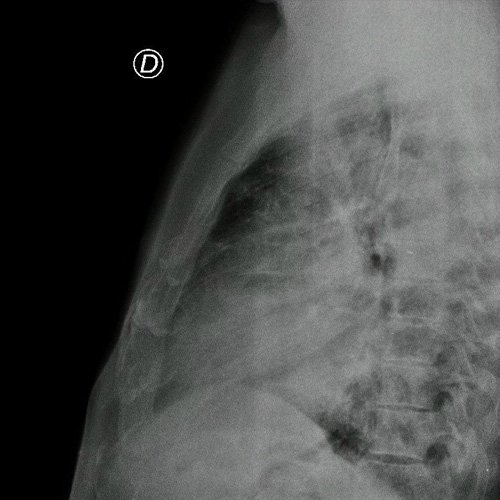

- Radiografía de tórax frente/perfil (Dia 0): rotada, bien inspirada, índice cardiotorácico impresiona conservado , se observa infiltrado parenquimatoso a nivel medio basal de campo pulmonar derecho e izquierdo, senos costofrénicos impresionan libres..

Radiografía de tórax frente y perfil

Radiografía de tórax frente y perfil